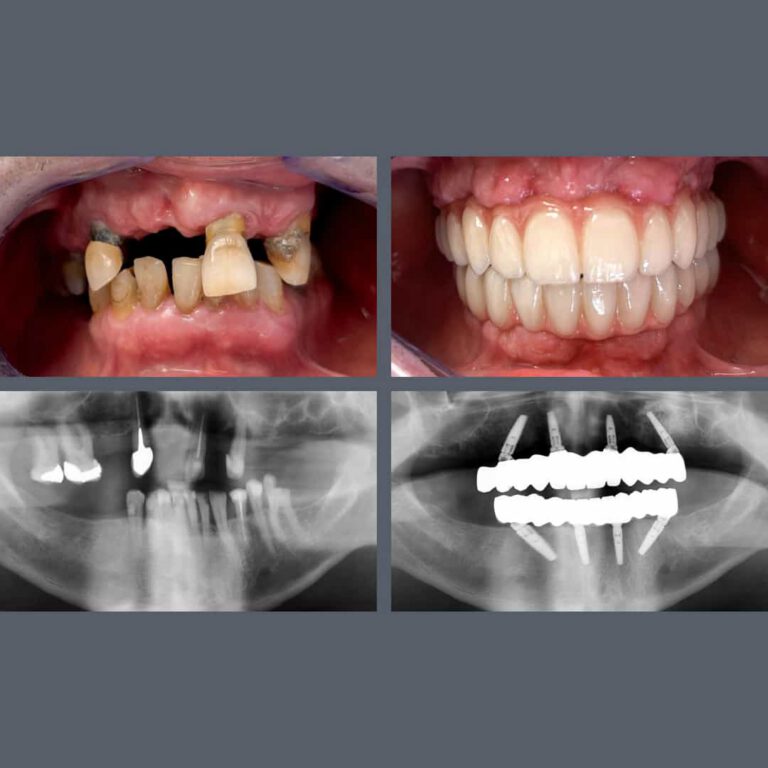

Tandimplantatproducenten Nobel Biocare har tildelt Madenta prisen “All-on-4® Center of Excellence”. Prisen gives til klinikken for det højeste antal All-on-4® behandlinger i Budapest og for enestående faglighed på højeste niveau.

Med denne anerkendelse regnes vores tandlæger blandt de førende specialister i Ungarn inden for All-on-4® behandlinger. Vi går ikke på kompromis og anvender udelukkende højkvalitets Nobel-implantater i vores All-on-4® behandlinger.

Specialiseret behandling giver smukke smil

Mange af vores udenlandske patienter kommer til os for implantater, kirurgiske indgreb og protetiske behandlinger, med håb om at kunne rejse hjem efter få dage med et både funktionelt og æstetisk smukt smil. Du er kommet til det rette sted! Vores specialister er internationalt anerkendte, og når de arbejder sammen på tværs af specialer, er næsten intet umuligt.